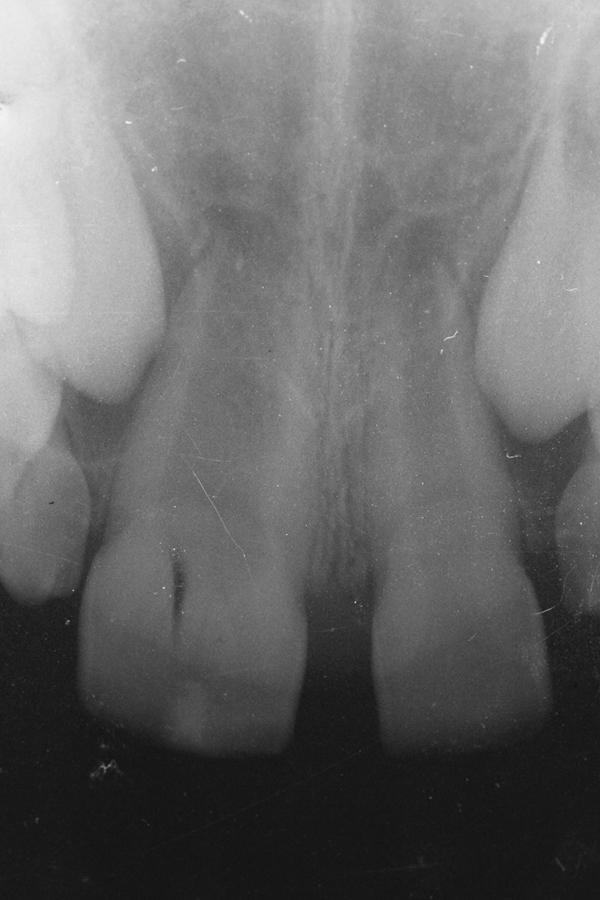

Fig 3. Radiographic scan of fused maxillary central-peg lateral incisors, teeth Nos. 7 and 8, and congenitally missing lateral incisor, tooth No. 10.

Figure 3

A 9-year-old girl, referred to a prosthodontic office by her pediatric dentist, presented with her mother’s chief complaint: “The kids are teasing her about her big front tooth.” Findings from radiographic and clinical examinations revealed fused maxillary central-peg lateral incisors, teeth Nos. 7 and 8, and a congenitally missing lateral incisor, tooth No. 10 (Figure 1 through Figure 3). An implant was selected as the ideal treatment to replace tooth No. 10 when somatic growth was complete. A diagnostic wax-up was fabricated to determine if the fused tooth could be made to resemble two teeth, using pink composite to give the illusion of an interproximal papilla. The patient was referred for an orthodontic consultation to plan for closure of the diastema between teeth Nos. 8 and 9 and achievement of proper alignment for implant No. 10. The patient was also referred to a periodontist for pretreatment assessment of the tooth No. 10 site. An endodontist was consulted should exposure of the large pulp occur during tooth preparation.